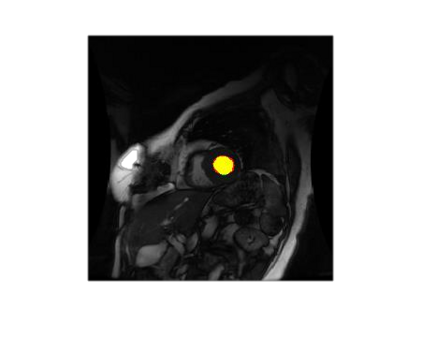

Deep Convolutional Neural Networks (DCNNs) are used extensively in biomedical image segmentation. However, current DCNNs usually use down sampling layers for increasing the receptive field and gaining abstract semantic information. These down sampling layers decrease the spatial dimension of feature maps, which can be detrimental to semantic image segmentation. Atrous convolution is an alternative for the down sampling layer. It increases the receptive field whilst maintains the spatial dimension of feature maps. In this paper, a method for effective atrous rate setting is proposed to achieve the largest and fully-covered receptive field with a minimum number of atrous convolutional layers. Furthermore, different atrous blocks, shortcut connections and normalization methods are explored to select the optimal network structure setting. These lead to a new and full-scale DCNN - Atrous Convolutional Neural Network (ACNN), which incorporates cascaded atrous II-blocks, residual learning and Fine Group Normalization (FGN). Application results of the proposed ACNN to Magnetic Resonance Imaging (MRI) and Computed Tomography (CT) image segmentation demonstrate that the proposed ACNN can achieve comparable segmentation Dice Similarity Coefficients (DSCs) to U-Net, optimized U-Net and hybrid network, but with significantly reduced trainable parameters due to the use of full-scale feature maps and therefore computationally is much more efficient for both the training and inference.